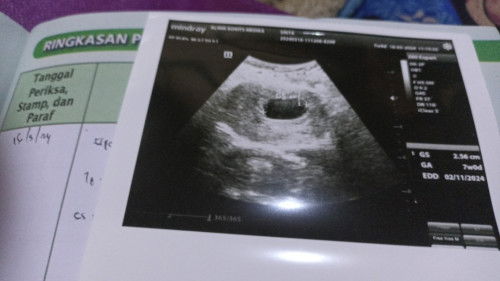

Hasil usg 7week belum terlihat janin 🥺

mungkin maksudnya bunda sekarang hamil 7w itu menurut hpht ya Bun? tapi kalau bener begitu pas USG emang baru kelihatan kantung, soalnya ada selisih antara hpht dan terjadinya pembuahan/penebalan rahim.. semangat bunda, semoga bunda dan debaynya sehat selalu 🙏☺️ aku dari hpht kemarin 9w4d pas di USG ternyata masih 7w3d.. selisih 2 Minggu, tapi Alhamdulillah udah aja janin dan djj nya ☺️ tetap positif thinking 💪

Baca lagisama bun aku kmren di usg 7w uda ada janin nyaa alhamdulih

Aku waktu hamil 7 week usg nya lewat vagina bun, alhamdullilah kelihatan jelas janinnya, kalo usg di perut nnti ketutupan lemak bun soalnya itu masih kecil bgt jdi disarankan usg lewat vagina

gapapa Bun, tunggu 3 Minggu lagi USG lagi insyaallah udah kelihatan janinnya, saya kemaren jg gitu USG 7 Minggu belum kelihatan janin, pas USG lagi udah kelihatan jelas bgt